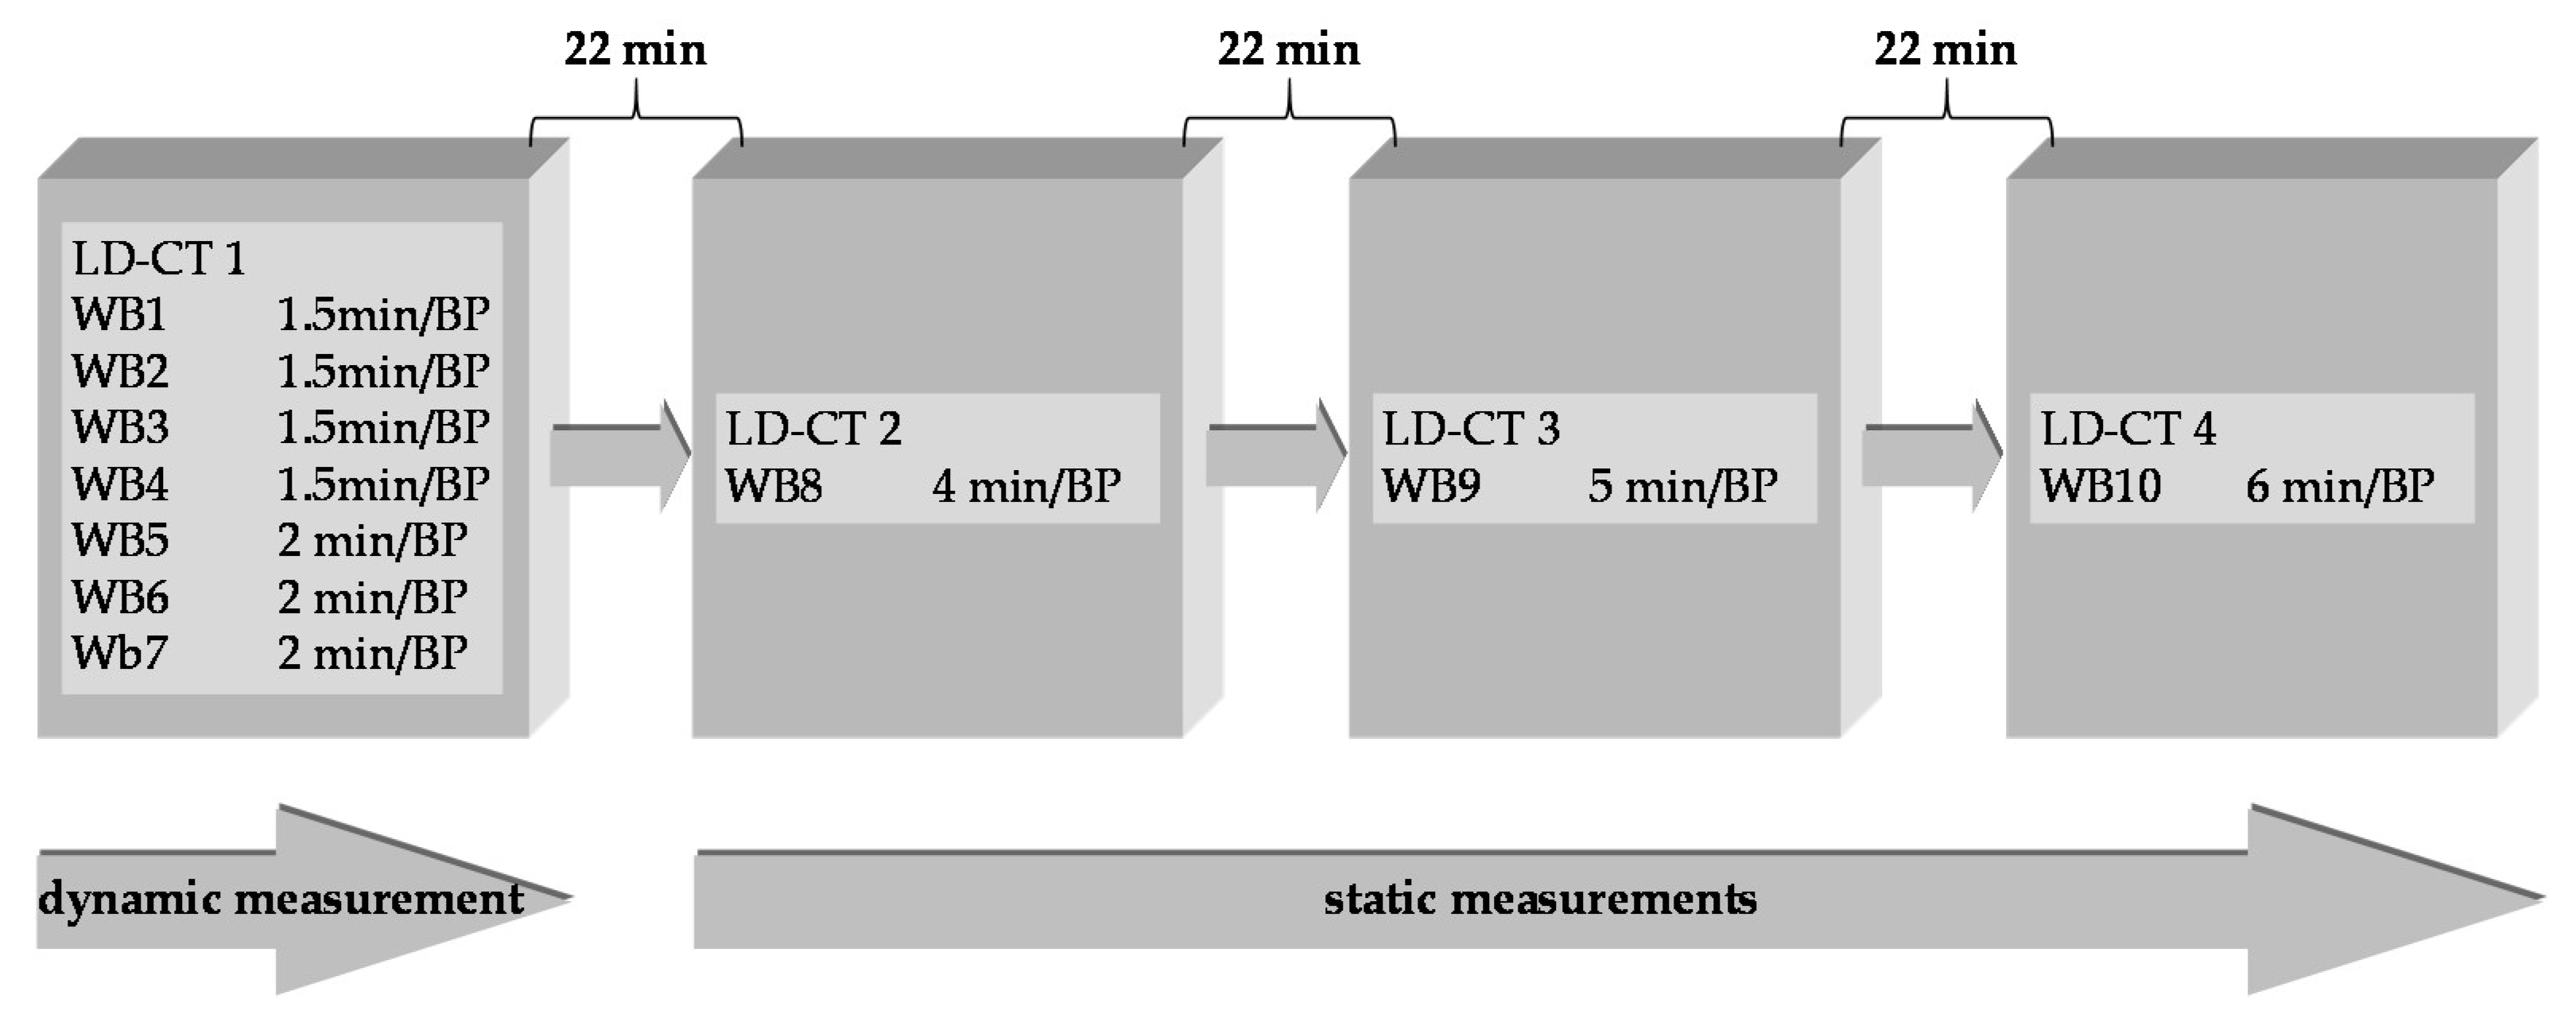

4.2. Preclinical Dosimetry Studies—In Vivo PET/CT Imaging in Pigs

4.3. Image Analysis

4.4. Incorporation Dosimetry